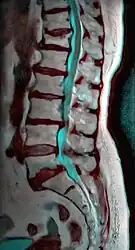

MRI

Magnetic resonance imaging (MRI) is the preferred advanced imaging technique for evaluation of spondylolisthesis.[26] Preference is due to effectiveness, lack of radiation exposure, and ability to evaluate for soft tissue abnormalities and spinal canal involvement.[26][27] MRI is limited in its ability to evaluate fractures in great detail, compared to other advanced imaging modalities.[28]

Degenerative spondylolisthesis at L5 - S1.

(A) CT sagittal view of a low grade slip.

(B) Lateral radiograph pre-operative intervention.

(C) Surgically treated with L5 – S1 decompression, instrumented fusion and placement of an interbody graft between L5 and S1.